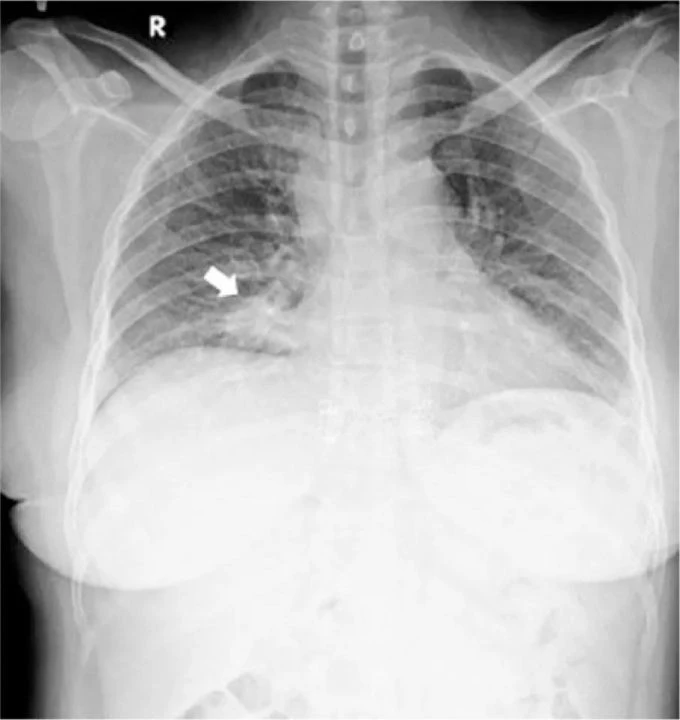

Kadının sol gözünde küçük büyümeler tespit edildi. Ayrıca kan testleri yapıldı ve kırmızı, beyaz kan hücresi sayımlarının normal aralıkta olduğu anlaşıldı. Doktorlar bir de göğüs röntgeni istedi ve akciğerinin sağ alt kısmında büyümeler tespit edildi.

Kanserden şüphelenen doktorlar, daha ileri tetkiklerde vücudundaki birçok organda tümör olduğunu fark ettiler. Kanser, metastaz yaparak her iki gözüne sıçradığı için bir gözünde körlüğe neden oldu.